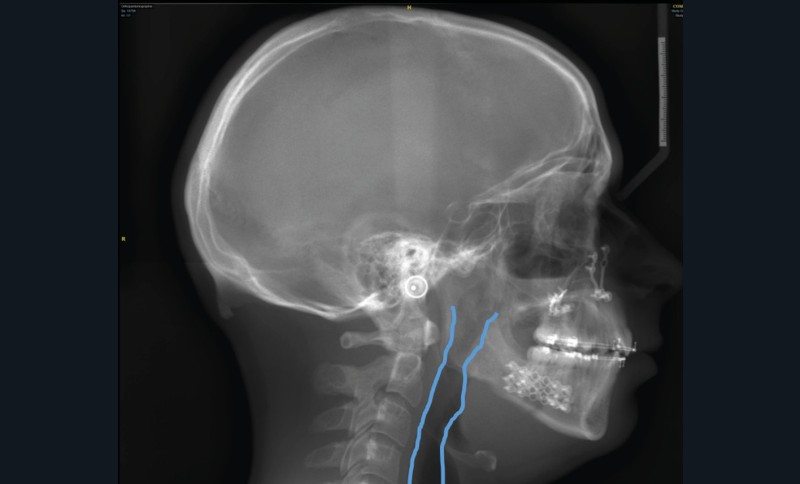

Le Dr Laïla Hitmi poursuivra dans le domaine des nouvelles technologies, en présentant l’ensemble des étapes d’un collage indirect, entièrement numérique : empreinte numérique et alignement avec le cone beam, positionnement virtuel des attaches orthodontiques, confection numérique et impression de la gouttière, transfert clinique.

Le début et milieu d’après-midi seront consacrés à l’empreinte numérique, désormais utilisée pour les empreintes d’étude, les set-up, le thermoformage. Les Drs Guillaume Lecocq et Stéphane Desplanques monteront le thermoformage et comment ces empreintes numériques peuvent permettre de confectionner des appareils vestibulaires, linguaux, voire des aligneurs (fig. 1 et 2).